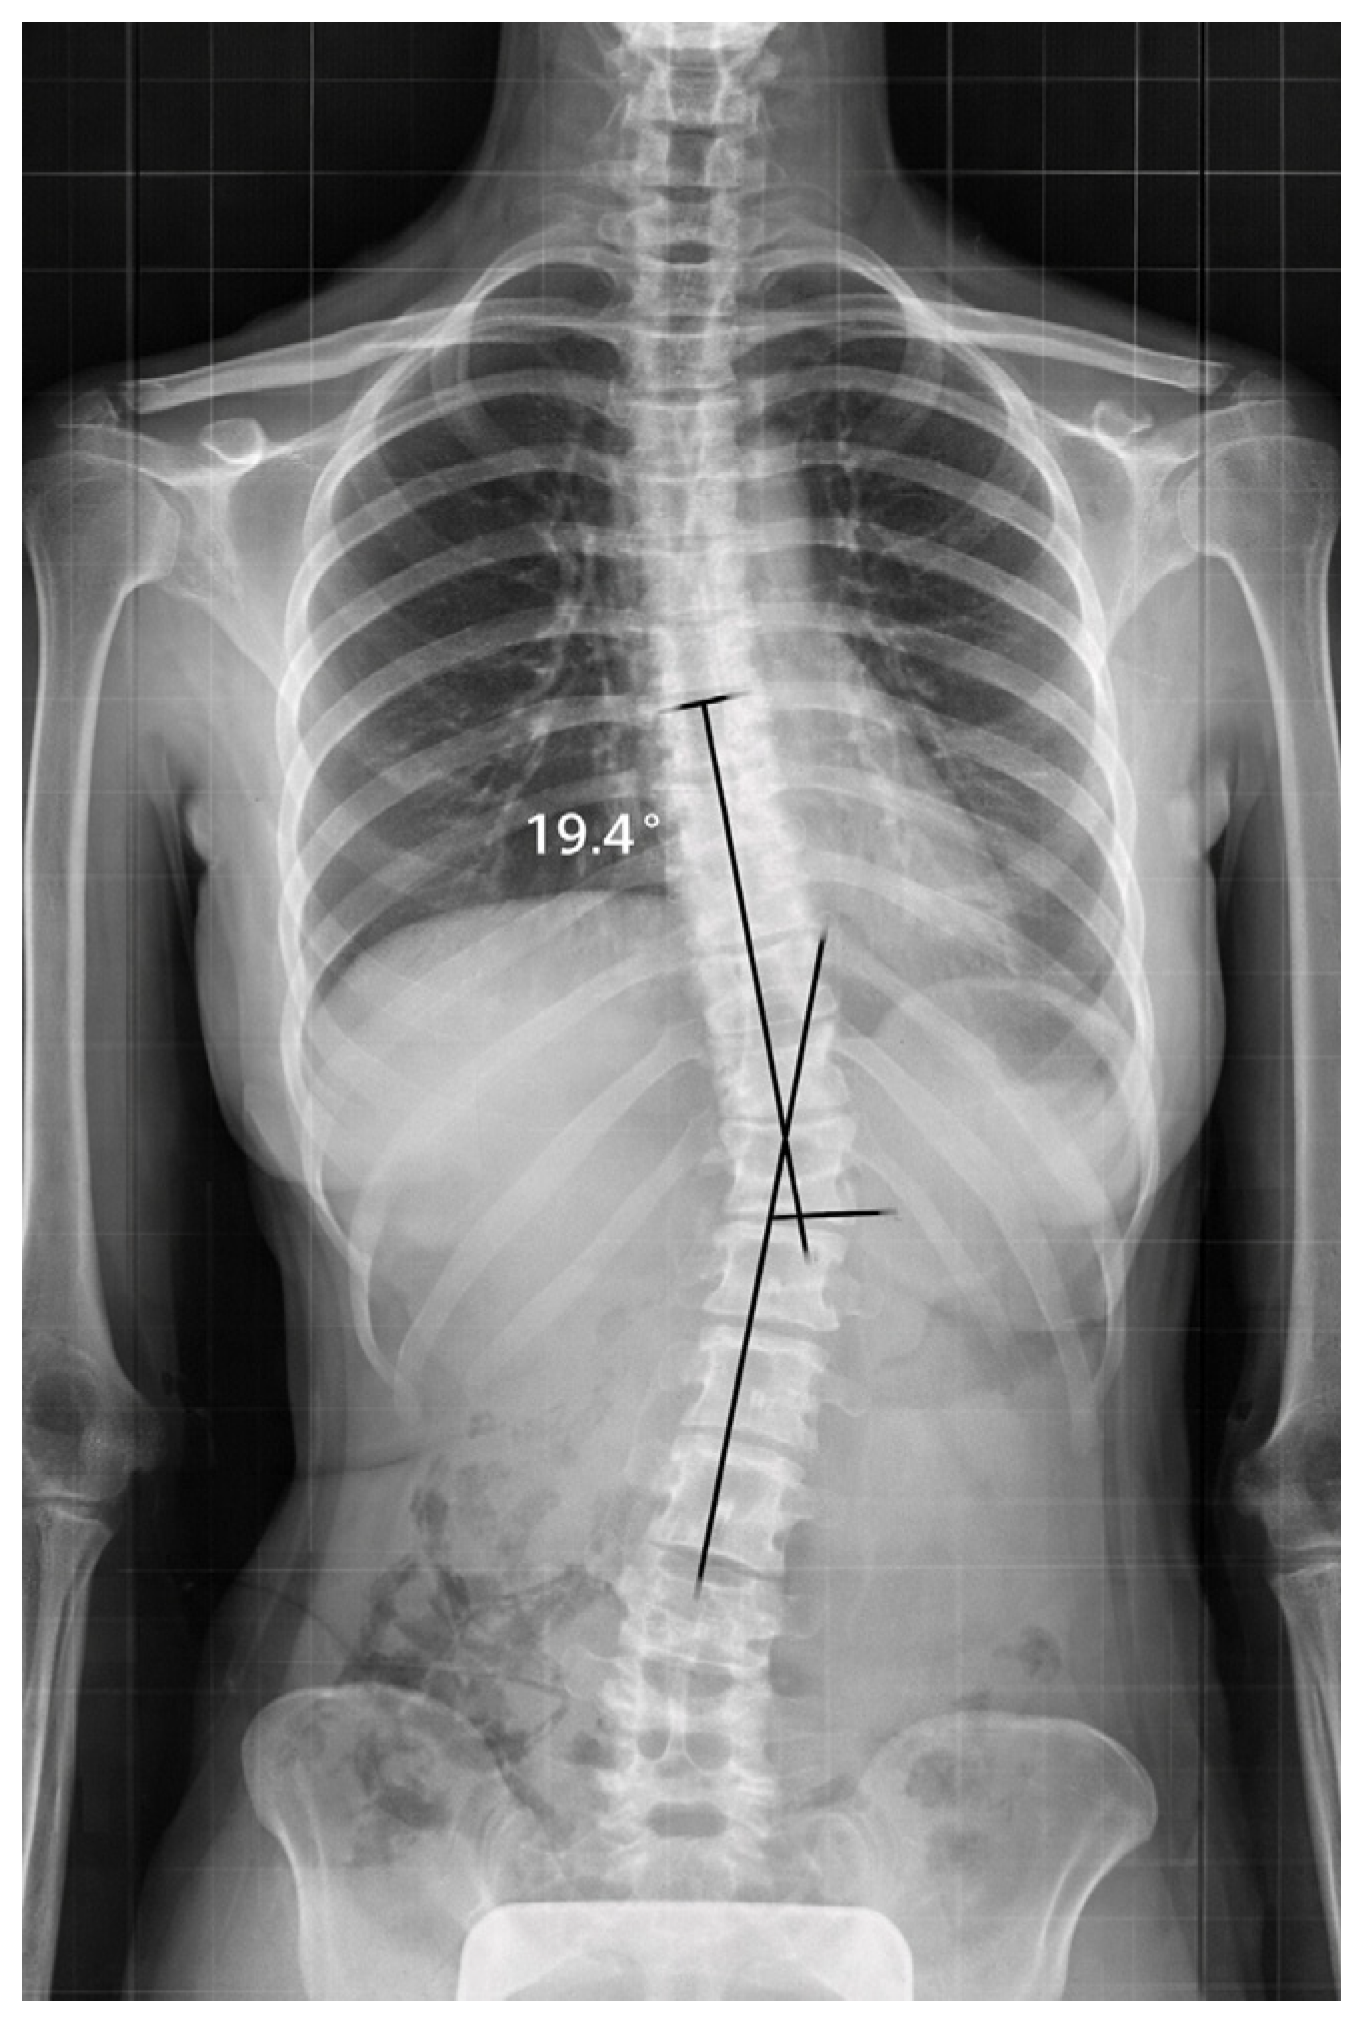

Standing spinal radiographs revealed left-convex thoracolumbar rotoscoliosis with the curved apex located between T12 and L1. The initial Cobb angle was 19.4°, consistent with a mild-to-moderate scoliotic deformity. Vertebral rotation was present, with a derotation angle ratio (DAR) of 1.9 (Figure 1).

Radiological evaluation also showed an asymmetry of pelvic alignment, with a discrepancy in height of the iliac crest of about 7.1 mm; a rectification of the thoracolumbar sagittal profile; and a preservation of cervical lordosis.

Skeletal maturity was assessed as Risser grade 4, indicating an advanced stage of skeletal development and a lower likelihood of spontaneous curve correction.

Overall, the findings were consistent with thoracolumbar AIS in an advanced stage of skeletal maturity.

At baseline, Case 1 showed a left-convex thoracolumbar curve with an apex at T12–L1. The Cobb angle was 19.4°, and vertebral rotation was documented with a DAR of 1.9. Pelvic asymmetry was also present.

Figure 1. Case 1: Basic standing anteroposterior spinal X-ray showing left-convex thoracolumbar scoliosis (Cobb angle 19.4°). Black lines indicate Cobb angle measurement performed by the radiologist between the upper and lower end vertebrae of the curve.